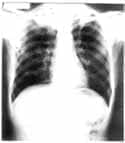

Se practicaron seis baciloscopias, todas reportaron negativo para BAAR. TAC AR de tórax (Figura 2) lesiones cavitadas de pared gruesa, simétricas en los segmentos apicales de los lóbulos superiores con consolidación parenquimatosa asociada.

Imágenes nodulares centrolobulillares e imágenes de árbol en gemación en el segmento posterior de lóbulo superior derecho y apical del lóbulo inferior izquierdo. Opacidad parenquimatosa en banda con bronquios dilatados en el segmento inferior de la língula.

Figura 2.